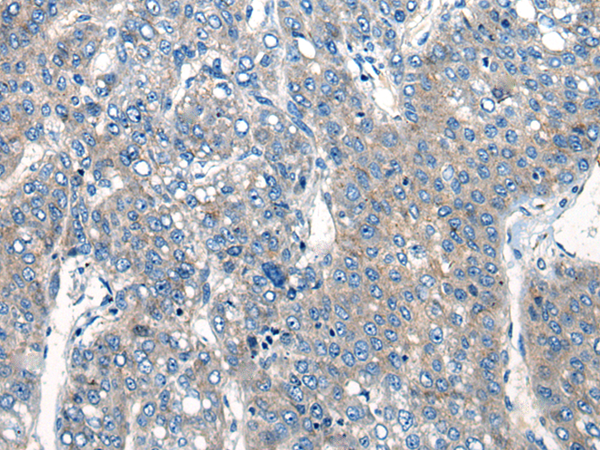

IHC positive control: |

Human liver cancer and human thyroid cancer |

IHC Recommend dilution: |

20-100 |